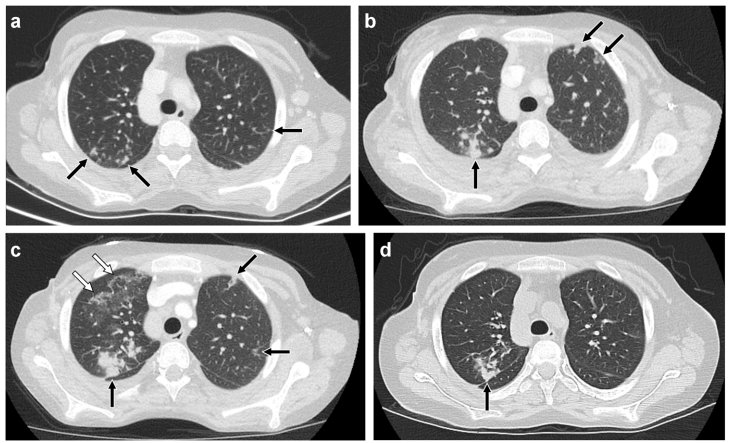

本综述系统阐述了儿童药物性肺病(Medication-induced Lung Disease)的影像学特征、临床诊断与管理策略,强调CT(Computed Tomography)在识别OP(Organizing Pneumonia)、DAD(Diffuse Alveolar Damage)、NSIP(Nonspecific Interstitial Pneumonia)等关键模式中的核心作用,为儿科放射科医生参与多学科诊疗提供实用指南。